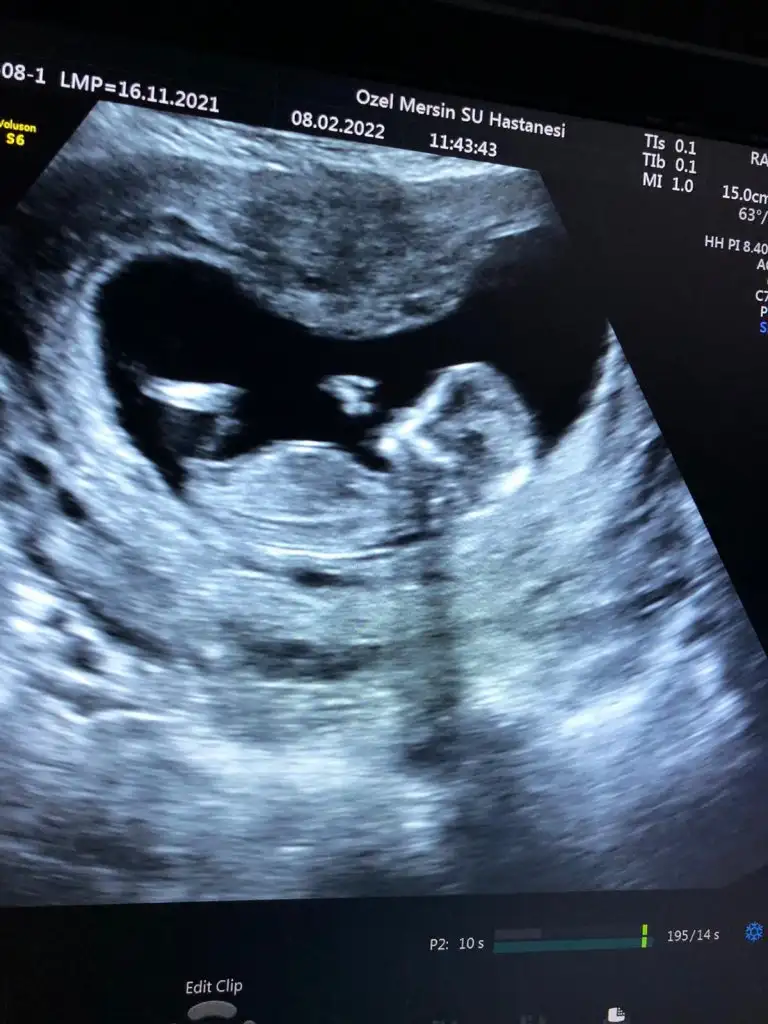

dr soylemeden siz gorun genital nub teorisi ( bebegin cinsiyeti)

Litfen benimkinede bakarmisin resimde 12 haftalik suan 16 dayim 18 haftamda gidicem ama merak ediyorum